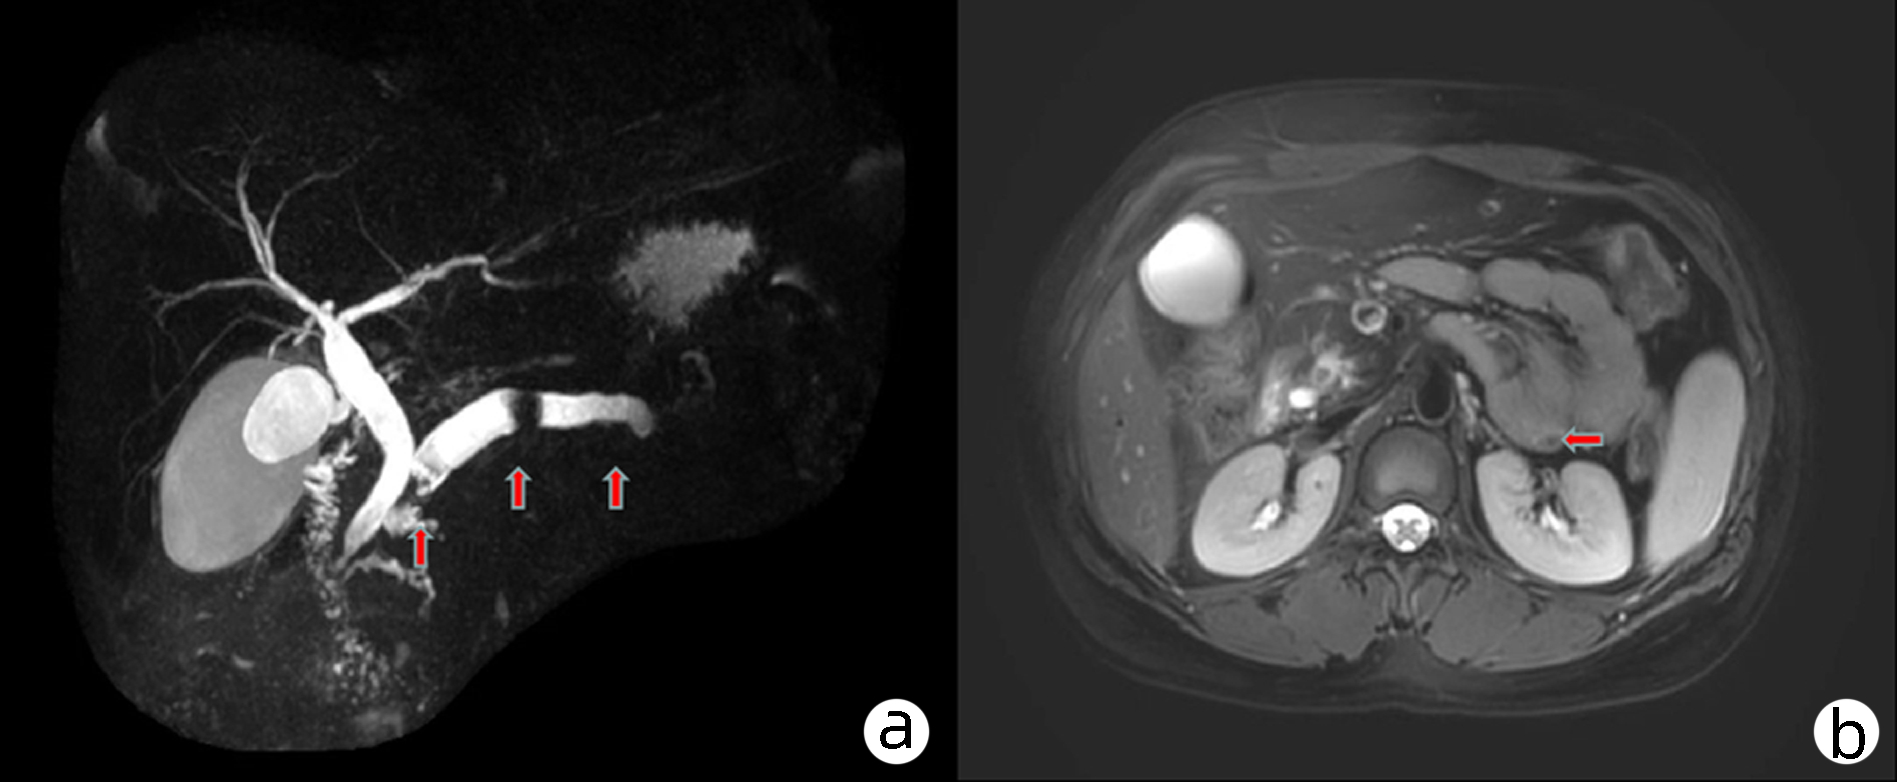

成人遗传性球型红细胞增多症诱发重度高胆红素血症1例报告

阿卜杜萨拉木·图尔荪麦麦提, 张云飞, 姚刚, 沙地克·阿帕尔, 吐尔洪江·吐逊, 温浩

2023, 39(8): 1922-1925. DOI: 10.3969/j.issn.1001-5256.2023.08.023

摘要(1449) HTML (311) PDF (2217KB)(116)

摘要:

遗传性球型红细胞增多症是一种人体红细胞膜缺陷遗传性溶血疾病,主要以贫血、黄疸、脾大为主要症状,因临床症状不典型,容易误诊漏诊,目前临床上总胆红素及直接胆红素极高病例较少见,国内外很少有报道,文本患者入院接受治疗时总胆红素高达1 686.01 μmol/L,直接胆红素高达1 166.6 μmol/L。经外科治疗该患者顺利出院,术后随访一般情况佳,生活质量高,本文总结了外科治疗遗传性球型红细胞增多症的相关诊疗经验。